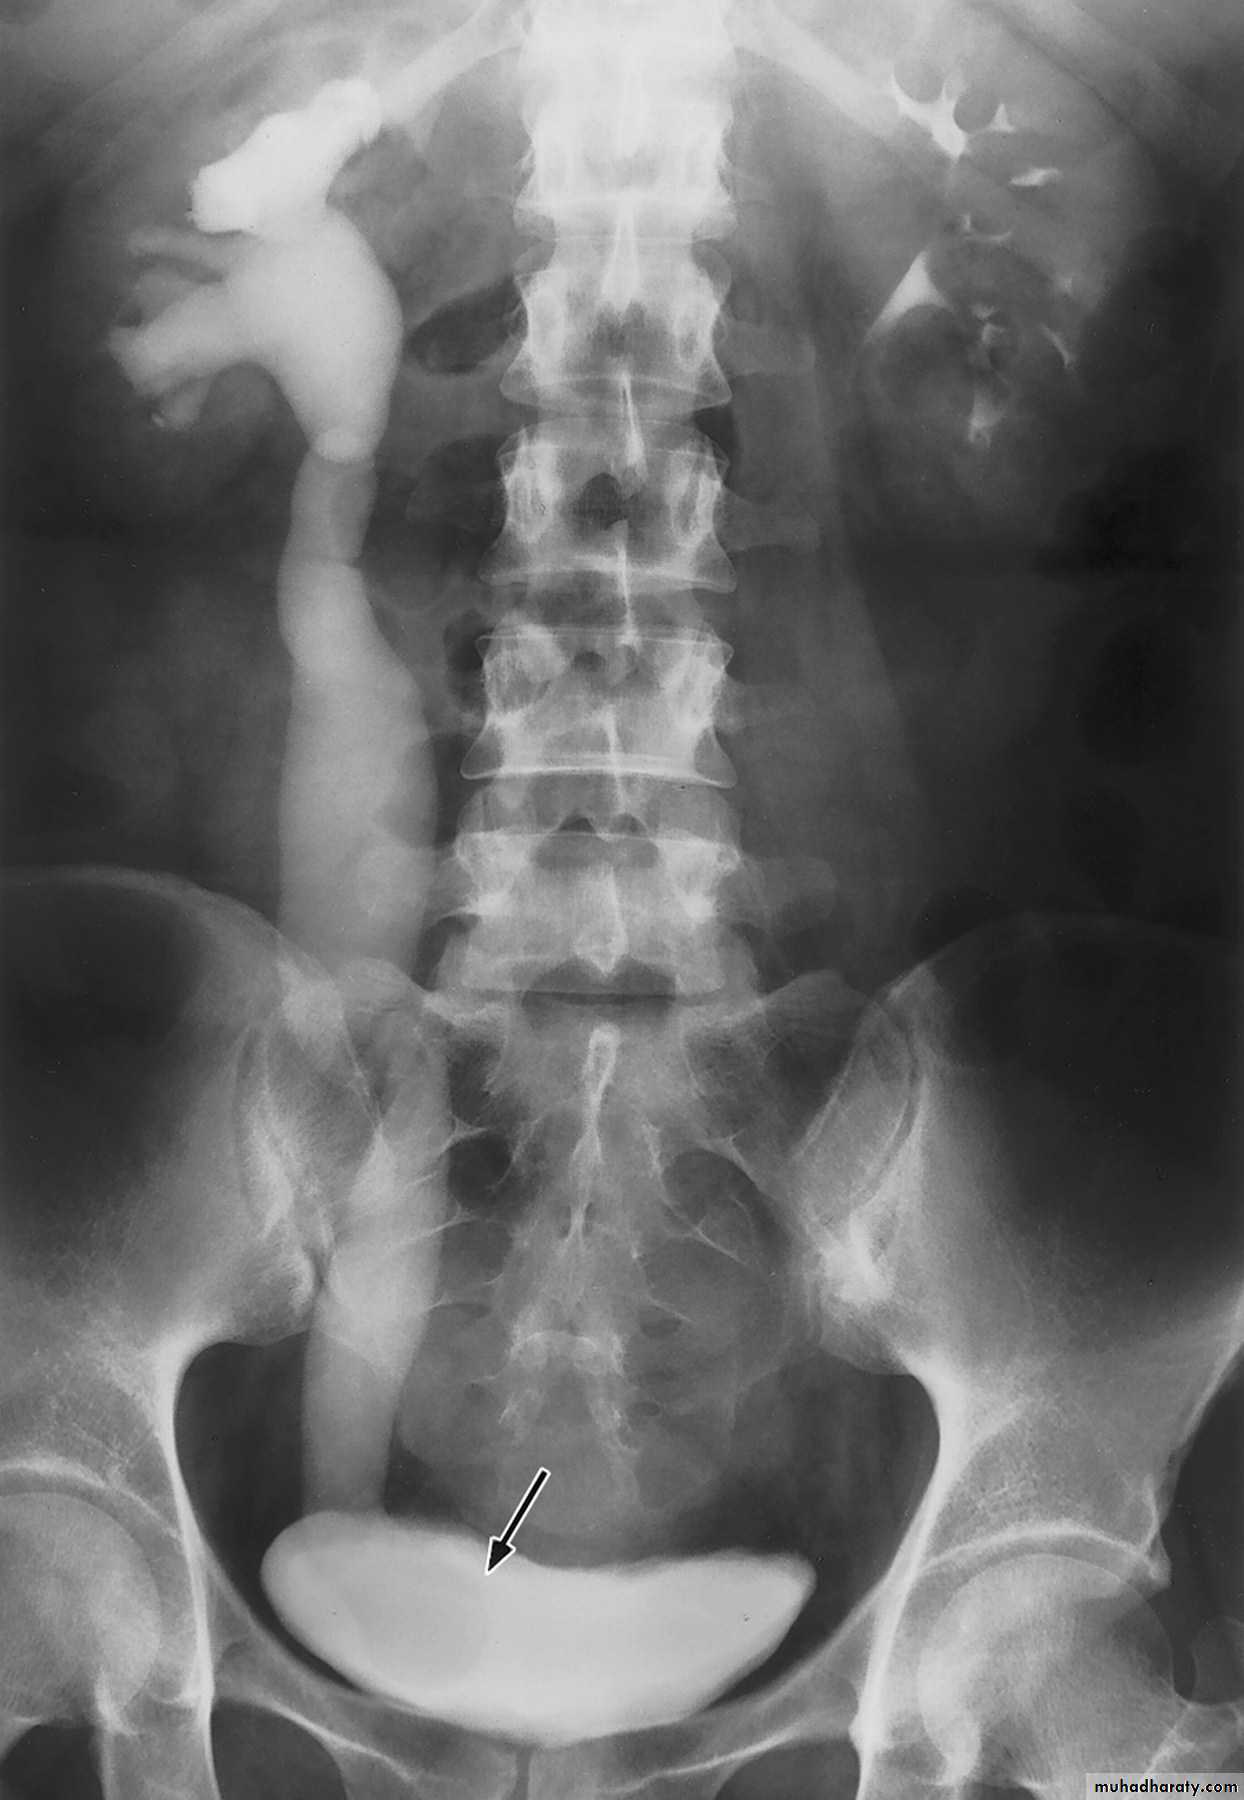

Plain abdominal film (KUB): may detect stone.

Intravenous urography (IVU): reveals hydronephrosis and its level and may also show the underlying cause. It requires good preparation and the injection of a contrast material which may cause allergy.

IVU Showing unilateral (left) hydronephrosis - PUJOIVU Showing unilateral (right) hydroureteronephrosis